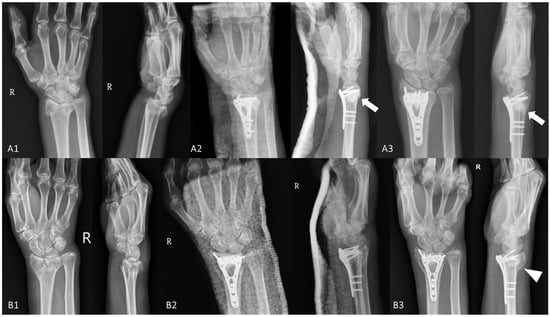

3.4. Our Experiences